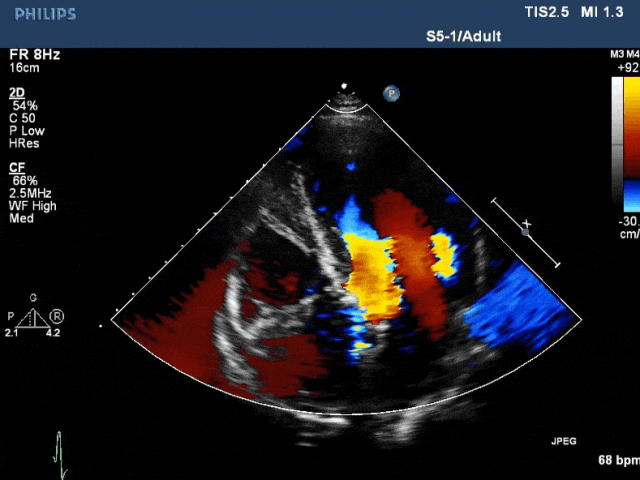

心脏超声

回顾经胸超声心动图图像时,观察到左心室与主动脉瓣上之间可能存在交通。